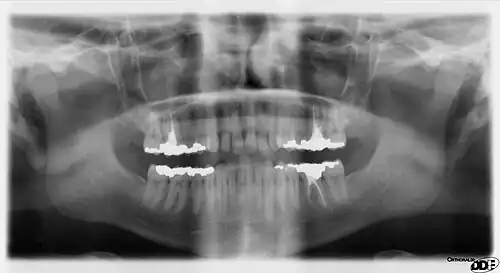

X-ray64A

Arrows point to two vertical white lines which is how calcifications in the first part (proximal component) of the internal carotid artery appear on panoramic radiographs.

Panoramic radiographs have the capability to demonstrate a portion of the neck and display atheromas (calcifications in the carotid artery) which are an indication of both local and generalized (systemic) atherosclerosis. Atherosclerosis of the coronary arteries leading to myocardial infarction (heart attack), and atherosclerosis of the carotid artery leading to stroke are the number one and number three most common causes of death in the United States.[6]

There is interest to look at panoramic radiographs as a screening tool, however further data is needed with regards if it is able to make a meaningful difference in outcomes.[7]